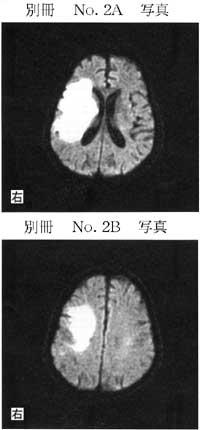

65歳の男性。意識が消失し緊急入院となった。発症後2日目においても意識障害は重度である。MRI拡散強調画像(別冊No.2A、B)を別に示す。この時点で行う管理で誤っているのはどれか。

1

座位耐久性訓練

2

肩関節の可動域訓練

3

2時間毎の体位変換

4

下腿三頭筋のストレッチ

5

下腿に弾性ストッキング装着